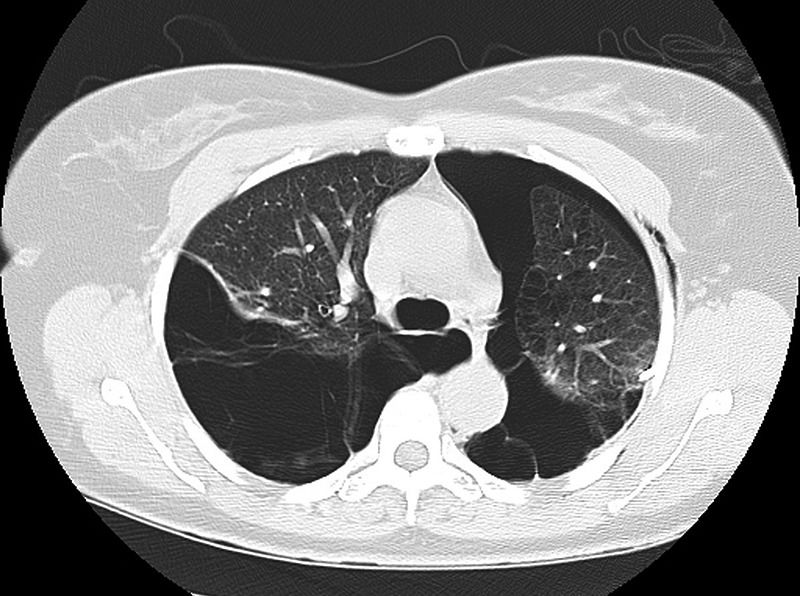

最后经影像学检查证实为消失肺综合征(Vanishing lung syndrome)导致的双侧气胸(见图6)。

图6 影像学证实双侧气胸